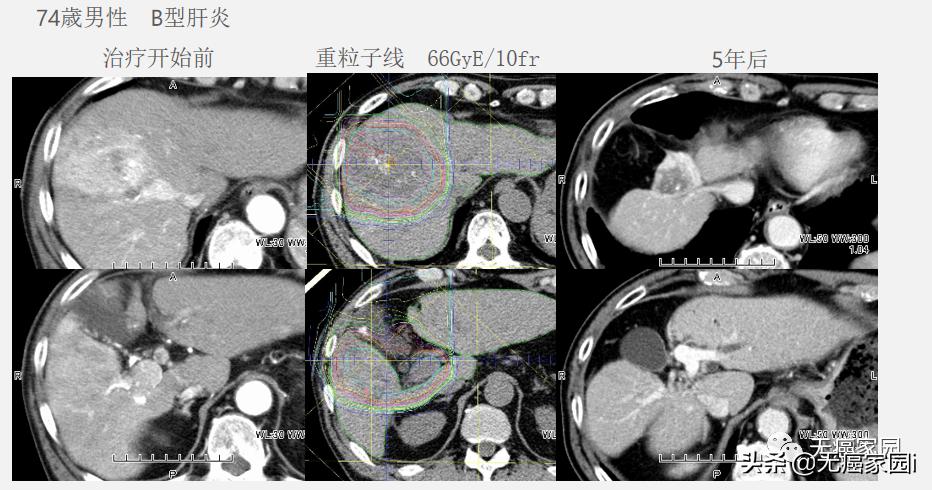

2.伴随着门静脉癌栓的肝细胞癌: 由于无法手术切除、无法采用动脉灌注治疗,因此只能使用粒子线期待根治。下图中的74岁男性患者发生门静脉癌栓,仅剩半年寿命,经粒子线治疗后存活5年以上,因此治疗效果甚好!

3.留置隔离垫手术: 在肿瘤和消化器官之间放置隔离垫进行隔离,这样可以使用更加强烈的照射射线量,来达到更好的治疗效果。